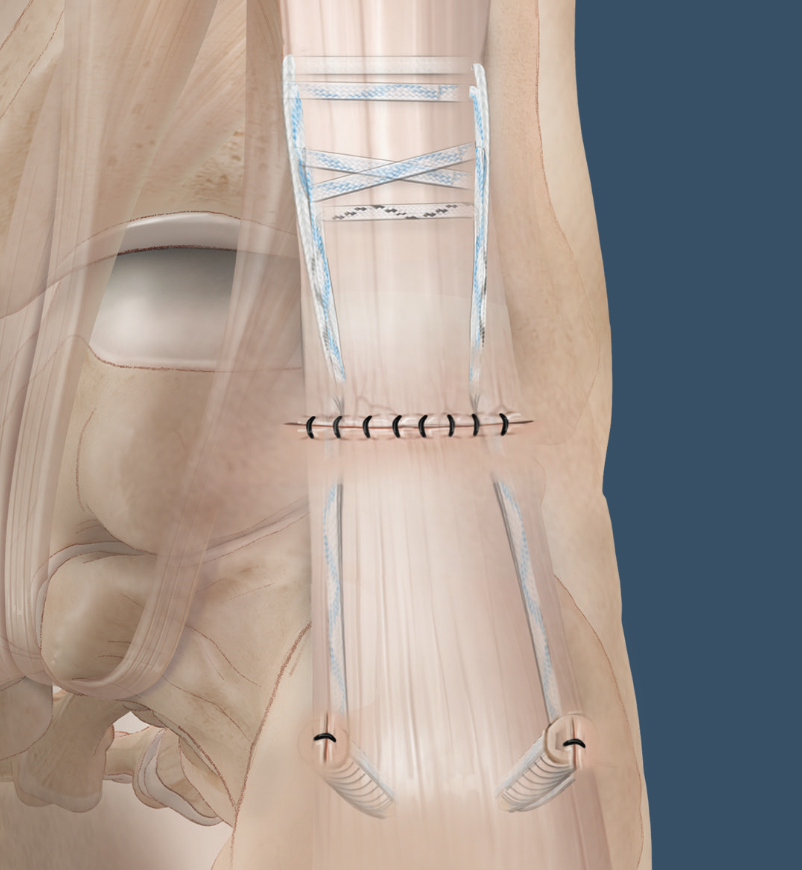

Minimally invasive repair

Percutaneous suture technique

Arthrex PARS

Vumedi percutaneous repair video

Calcaneal anchor technique

Arthrex Speedbridge technique

Vumedi Arthrex Speedbridge in calcaneum

Vumedi stryker anchors in calcaneum video